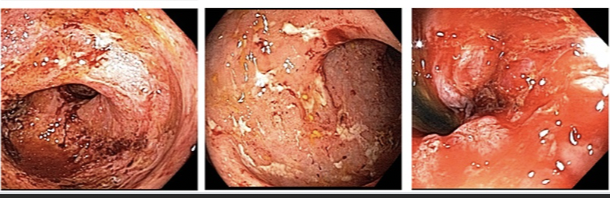

Colon biopsy

low grade dysplasia

Chronic colitis

altered crypt architecture (branching crypts)

microabcesses